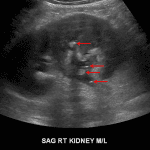

Ultrasound